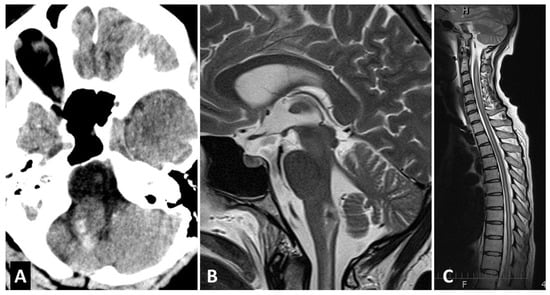

2. Case Report